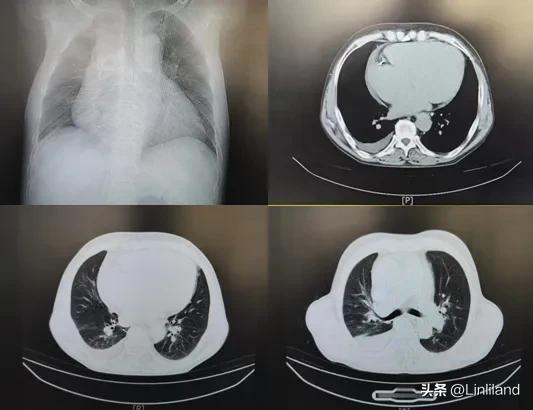

胸部CT片示心影扩大、双肺瘀血征,右侧可见少量胸腔积液

患者胸部CT示心影明显扩大、双肺瘀血征,右侧还有少量胸腔积液。再看患者的心电图,心电图示宽QRS波性心动过速,乍一看貌似“室性心动过速”,但RR间期不整,且心室率很快,差不多有170次/分,看上去有些恐怖,不过,患者奔波很远的路程能来看病且可以随意走动,综合判定应该是“快速性心房颤动(房颤)合并室内传导阻滞”,而绝非室性快速心律失常。再仔细察看患者的心电图,总觉得心电图有些异样。心电图显示的不仅仅是房颤,而且宽大畸形的QRS波形态不整、宽窄不一,心室率很快、约在160~180次/分,这些特点难道不是“预激综合征合并房颤”的心电图特征吗?然而,患者平素不查体、不上医院,连一份以往的心电图都没有可以用来作参照比较,一来看病心电图就是这个样子,一时还真难拎得清。